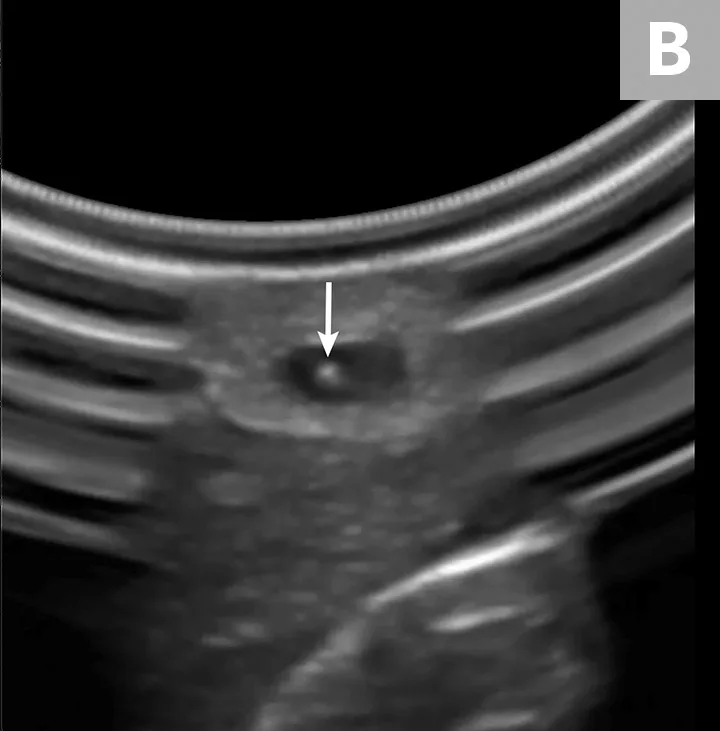

Insert the catheter needle and stylet into the skin at a 30- to 45-degree angle, just distal to the probe (A). Identify the needle tip as a white dot (B, arrow) on the display between the skin and the vessel, and stop advancing.

Ultrasound probe held over limb of pet and ultrasound image with arrow pointing to needle seen within blood vessel.